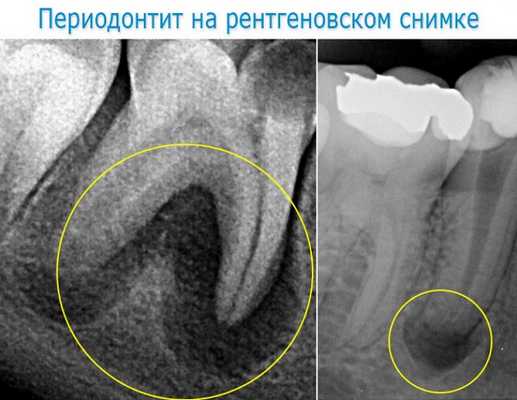

Окончательно диагноз хронического периодонтита устанавливается на основании данных радиовизиографии и электроодонтодиагностики. В некоторых клинических ситуациях может быть показана фистулография. В большинстве случаев распознавание хронического периодонтита возможно только с учетом интерпретации рентгеновского снимка зуба, где определяется разрежение костной ткани (иногда деструкция твердых тканей корня зуба) в области апекса. Пороговое значение электровозбудимости пульпы при хроническом периодонтите превышает 100 мкА.

- Рентгенография зуба. В случае хронического гранулирующего периодонтита в апикальной области обнаруживается участок разрежения костной ткани с нечеткими границами размерами от 1 до 8 мм. Хронический гранулематозный периодонтит характеризуется ясно очерченными округлыми контурами области разрушения костной структуры вокруг верхушки корня зуба. Хронический фиброзный периодонтит на рентгенограмме проявляет себя расширенным периодонтальным пространством в апикальной области при отсутствии резорбции костной стенки альвеолы.